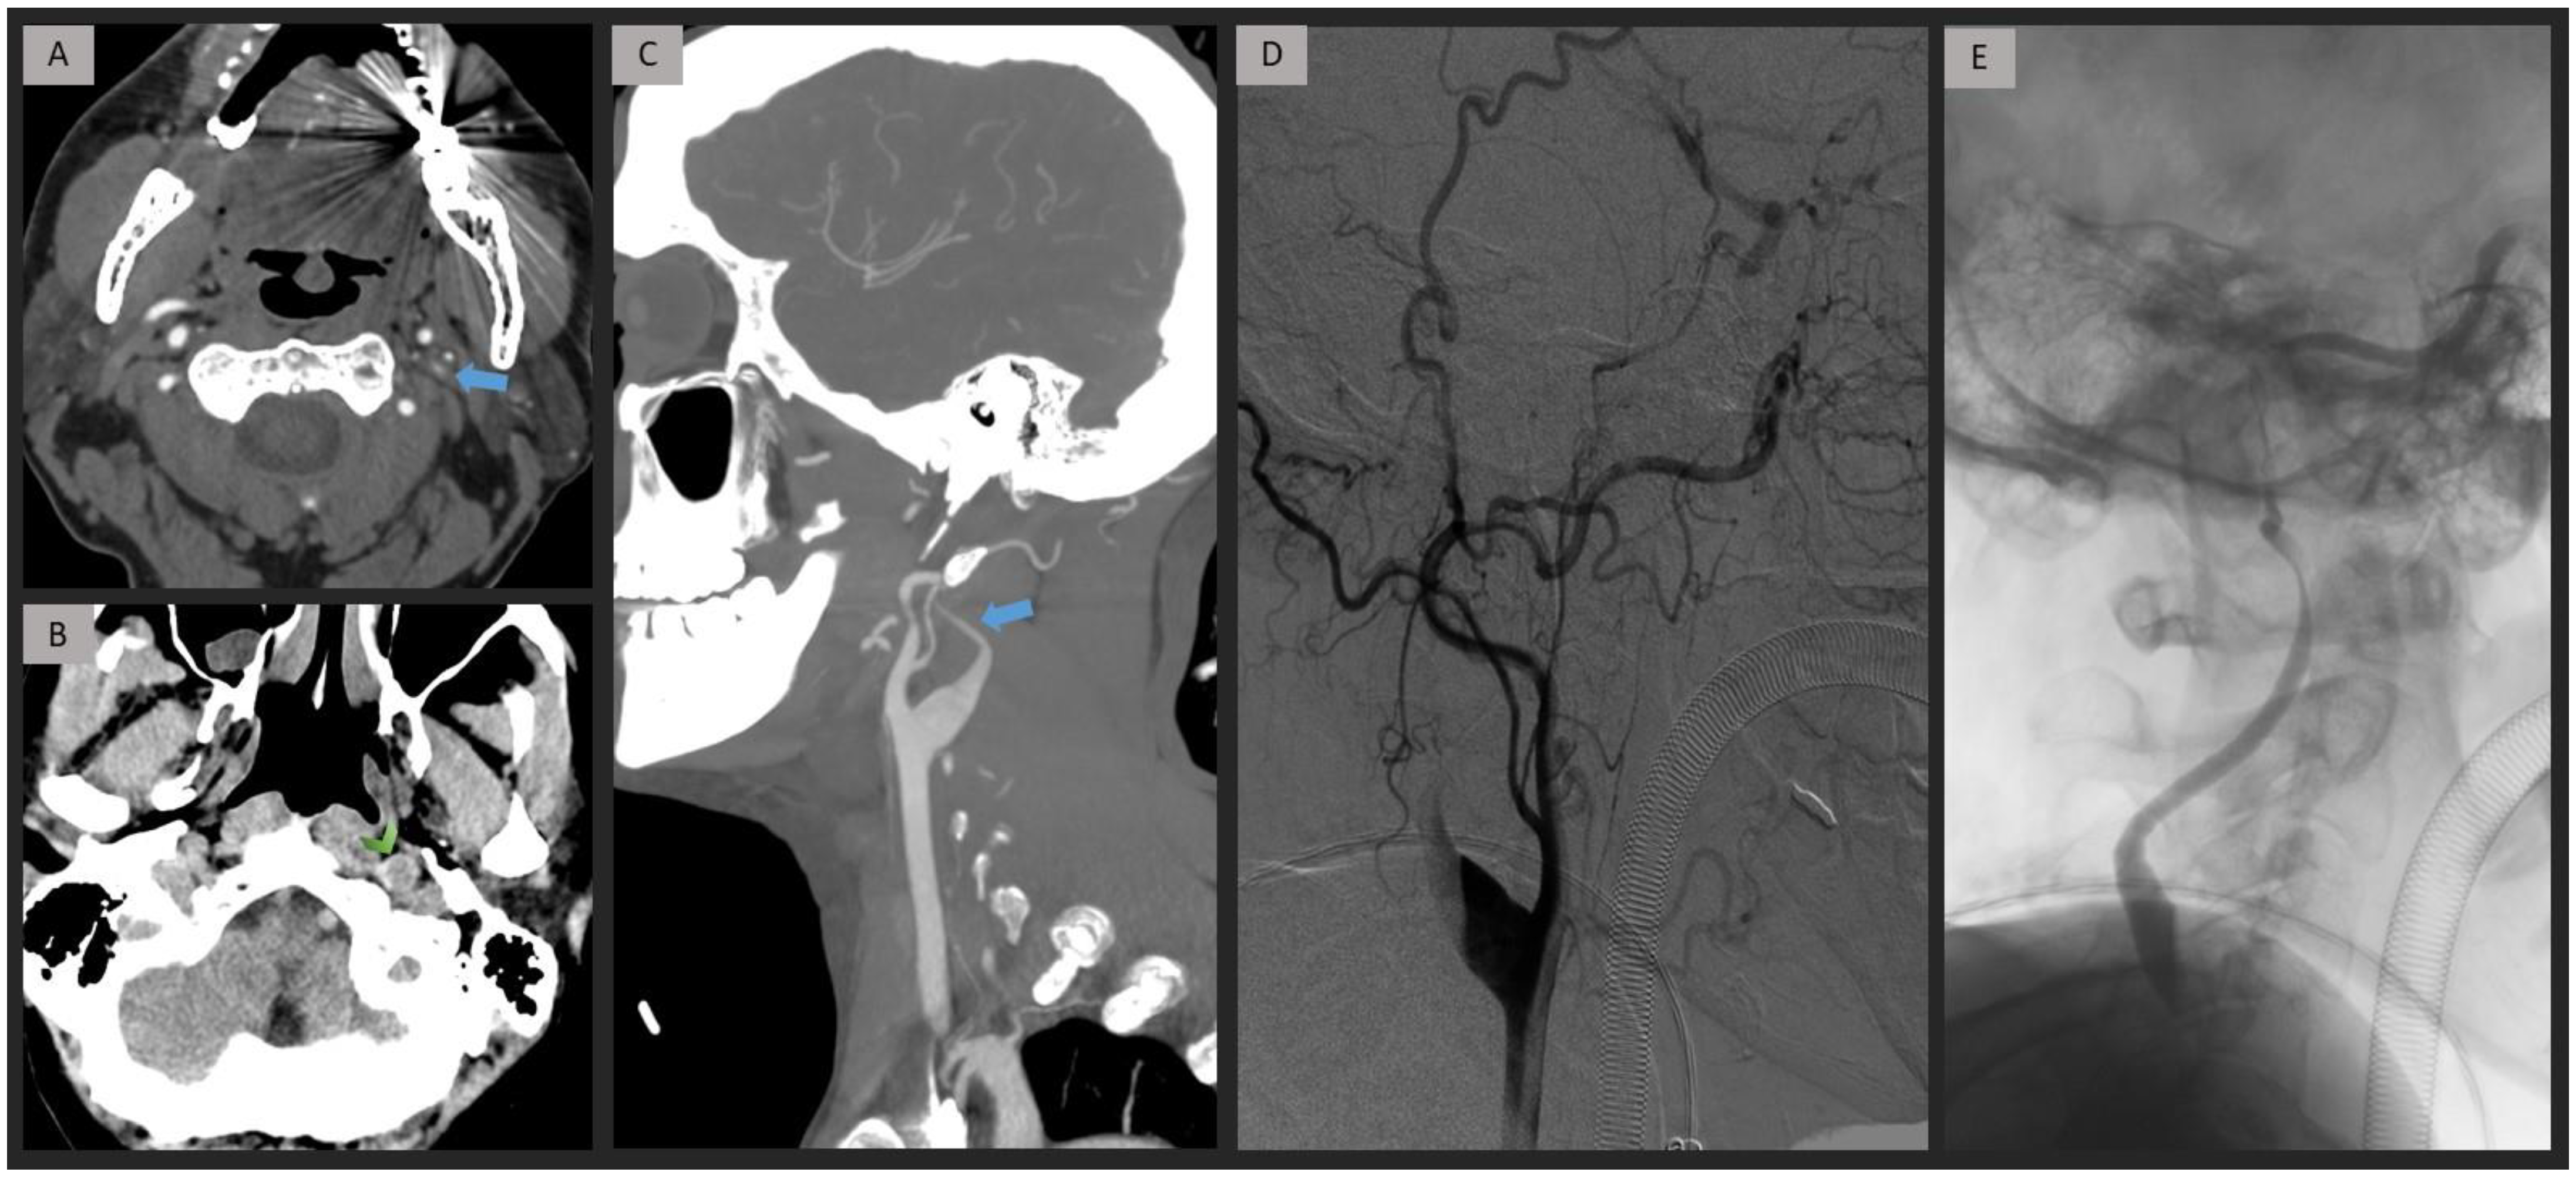

Figure 4.

Patient presenting with left extracranial ICA occlusion caused by dissection. Axial and Sagittal-MIP CTA images (A,C) demonstrate a progressive contrast decay and stenosis of the cervical ICA, associated with an arterial widening (blue arrow). NCCT (B) reveals a wall hematoma in the left ICA near the skull base (green arrowhead). DSA (D) and fluoroscopy (E) confirm the diagnosis of cervical ICA dissection. ICA = internal carotid artery; NCCT = non-contrast computed tomography; MIP = maximum intensity projection; CTA = computed tomography angiography; DSA = digital subtraction angiography.